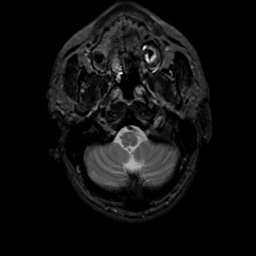

MR Study #22, December 1, 1991 -- Slice #5